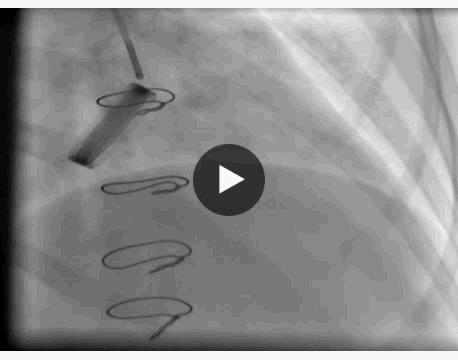

冠脉造影显示:左主干未见明显异常,前降支近中段动脉硬化,未见明显狭窄及血栓,远端血流TIMI 3级,回旋支全程可见散在斑块,近段局限性狭窄约50%,远段血栓影消失,远端前向血流TIMI 3级。

右冠脉动脉硬化,近中段可见多处局限性斑块病变轻度狭窄,远端血流TIMI 3级。 结论:符合冠心病、急性心肌梗死改变,目前回旋支远段血栓自溶,未见明显狭窄病变,暂不予以支架植入。

主要造影结果

月经期结束后复查冠脉造影显示,回旋支远段血栓影消失,远端前向血流TIMI 3级。